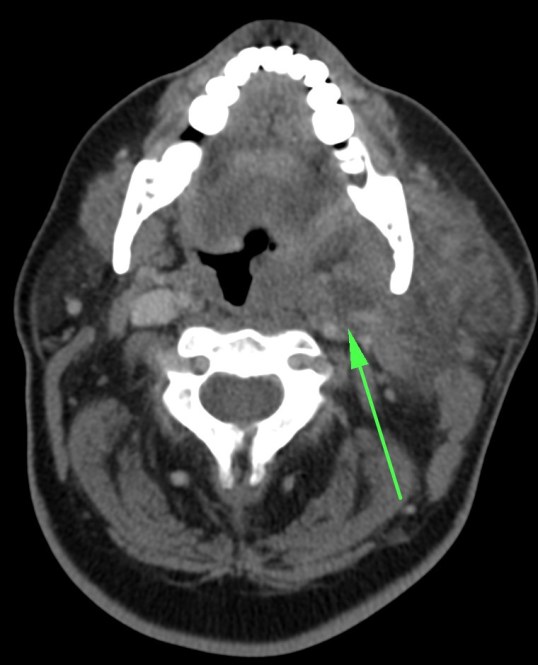

LINFADENITIS CERVICAL

Afectación inflamatoria-infecciosa del tejido linfoide cervical.

Mayor prevalencia en inmunosuprimidos.

Clínica: masa cervical + fiebre, dolor, signos de flogosis local.

TC con contraste:

- Ganglios aumentados de tamaño con o sin necrosis central asociada, uni o bilaterales que pueden confluir formando masacotes adenopáticos en una o más de las cadenas linfáticas cervicales.